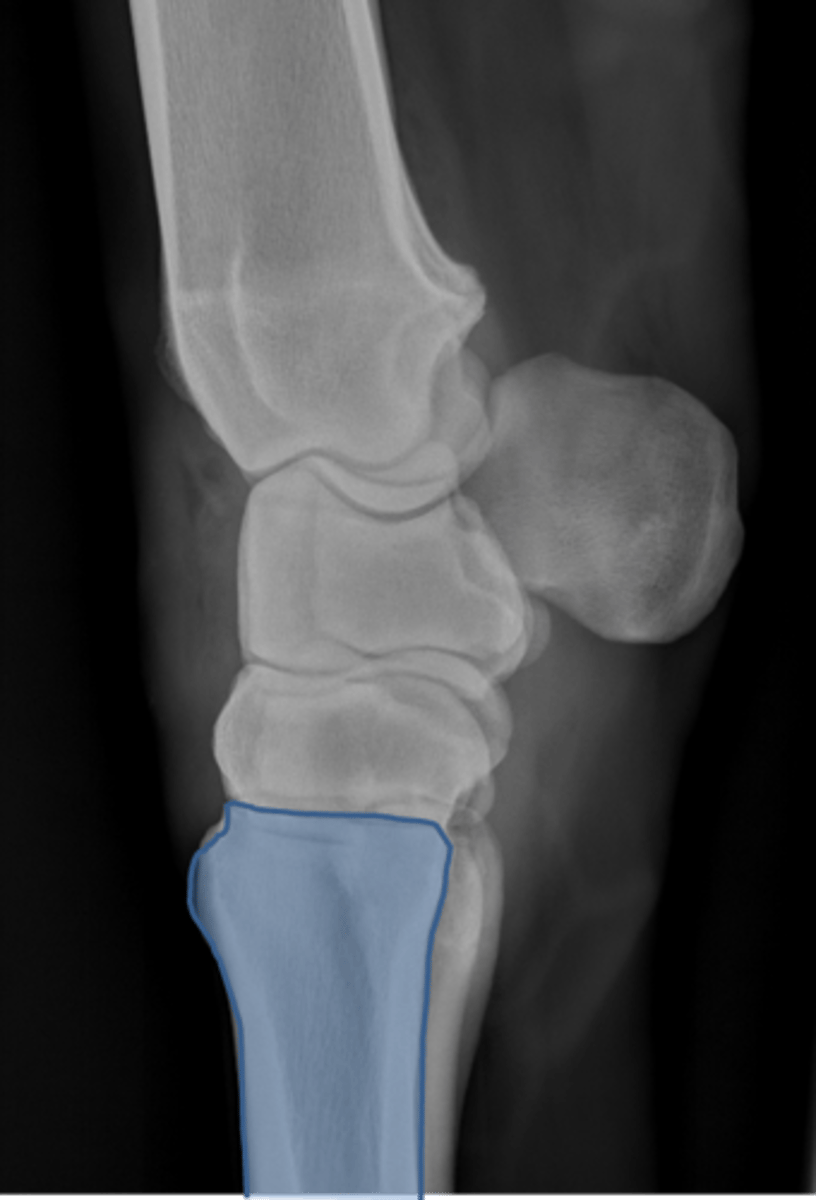

Carpus, lateral

ID joint and view

Antebrachiocarpal joint

Middle carpal joint

Carpometacarpal joint

Radial carpal bone

Intermediate carpal bone

Ulnar carpal bone

Third carpal bone

Second carpal bone

Fourth carpal bone

Accessory carpal bone

Second metacarpal (medial splint)

Fourth metacarpal (lateral splint)

Cannon bone